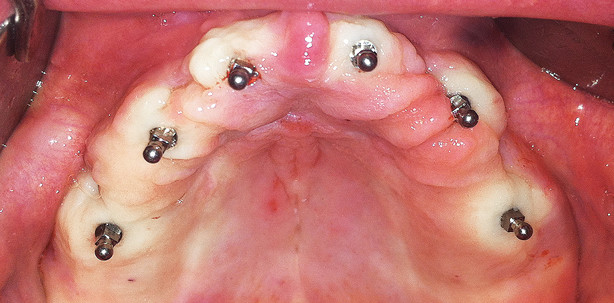

Zur Vorbereitung wurde zunächst eine Panoramaschichtaufnahme durchgeführt (Abb. 1). Die Implantationsalveolen sind auf dieser noch deutlich erkennbar. Um die Mini-Implantate nicht in die Alveolen zu inserieren und das vorhandene Knochenangebot optimal auszunutzen, erfolgte anhand der Aufnahme eine sorgfältige Planung der Positionierung. Dabei zeigte sich, dass die Mini-Implantate aufgrund des ausreichend vorhandenen Knochenangebots an den Idealpositionen in Regio 16, 14, 12, 22, 24 und 26 gesetzt werden konnten, sodass die prothetische Belastung sehr ausgewogen sein würde. Nach Übertragung der Planung in den Patientenmund – hierzu wurde eine Tiefziehschiene mit Bohrungen an den entsprechenden Stellen verwendet und mit einer Sonde jeweils eine leichte Blutung hervorgerufen – kam der Pilotbohrer zum Einsatz. Dieser Bohrer für die Einmalanwendung mit einem Durchmesser von 1,1 mm wird verwendet, um bis zu einer Tiefe von einem Drittel bis der Hälfte der Implantatlänge zu bohren, danach werden die Implantate mit selbstschneidendem Design direkt in den Knochen eingedreht. Durch die erzeugte Kompression und Kondensation des Knochens wird eine höhere Primärstabilität der MDI erzielt. Danach erfolgte die transgingivale Insertion der sechs Implantate nacheinander unter Verwendung von Verschlusskäppchen, Initialschraubendreher, Flügelschrauber und Drehmomentratsche (Abb. 2–4). Abbildung 5 zeigt das Ergebnis des chirurgischen Eingriffs, Abbildung 6 das Kontroll-OPG.

Die Basis der metallverstärkten Prothese wurde ausgeschliffen und mit weichem Unterfütterungsmaterial versehen (Abb. 7 und 8), um die Patientin direkt prothetisch versorgen zu können, ohne eine Überlastung und somit das erneute Auftreten von Periimplantitis zu riskieren. Geplant ist, die Mini-Implantate vier Monate einheilen zu lassen, bevor die Metallgehäuse in die Prothese integriert werden. Abbildung 9 zeigt die eingesetzte Prothese im Patientenmund.